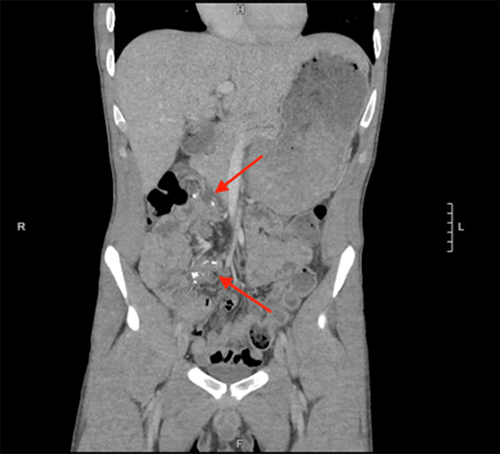

The patient presented with abdominal pain, diarrhea, vomiting, and oral intolerance and was admitted for presumed Crohn's flare with concern for possible stricture. He was started on intravenous steroids and underwent video capsule endoscopy, demonstrating inflammation and ulceration in the small intestine without stricture. However, his symptoms did not improve with IV steroids. After two weeks in the hospital, the patient had a sudden increase in abdominal pain and distension with worsening leukocytosis. The CT scan demonstrated dilated loops of small bowel in the left abdomen and decompressed loops in the right side of the abdomen, lateral to the colon, with a swirling of mesenteric vessels, indicative of an internal hernia with low-grade obstruction (Figure 2 and Figure 3).

Figure 2. CT Scan Demonstrating Ileocolic Anastomosis in Mid-Abdomen (Middle Arrow) With Substantial Amount of Small Bowel to Right Lateral of Anastomosis (Side Arrow). Published with Permission